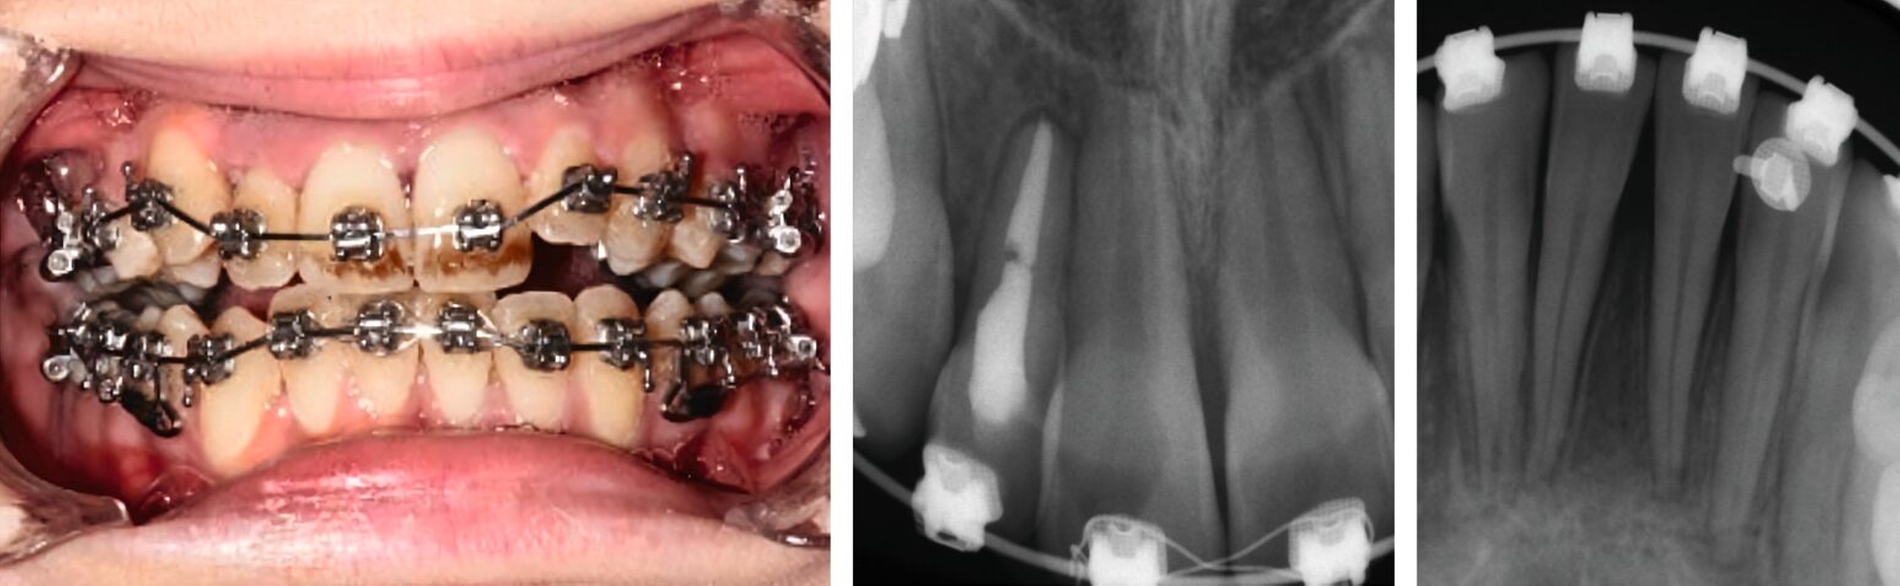

Intrusion

Intrudierte Zähne zeigen in einem hohen Prozentsatz eine infizierte Pulpanekrose (60 Prozent bei offenem Apex, 100 Prozent bei geschlossenem Apex), die mit einer aggressiven infektionsbedingten Wurzelresorption einhergeht (Abbildung 4). Der daraus folgenden Notwendigkeit zur endodontischen Behandlung sollte unter allen anderen Überlegungen Priorität eingeräumt werden. Intrudierte Zähne mit abgeschlossenem Wurzelwachstum sollen daher grundsätzlich bei der Erstversorgung in die anatomisch korrekte Position reponiert und dort geschient werden. Die nekrotische Pulpa sollte so früh wie möglich entfernt werden.

Bei Zähnen mit nicht abgeschlossenem Wurzelwachstum und bei geringfügiger Dislokation kann mit der Trepanation zugewartet werden. Engmaschige Nachkontrollen sollten eine Pulpanekrose oder eine externe Wurzelresorption ausschließen.